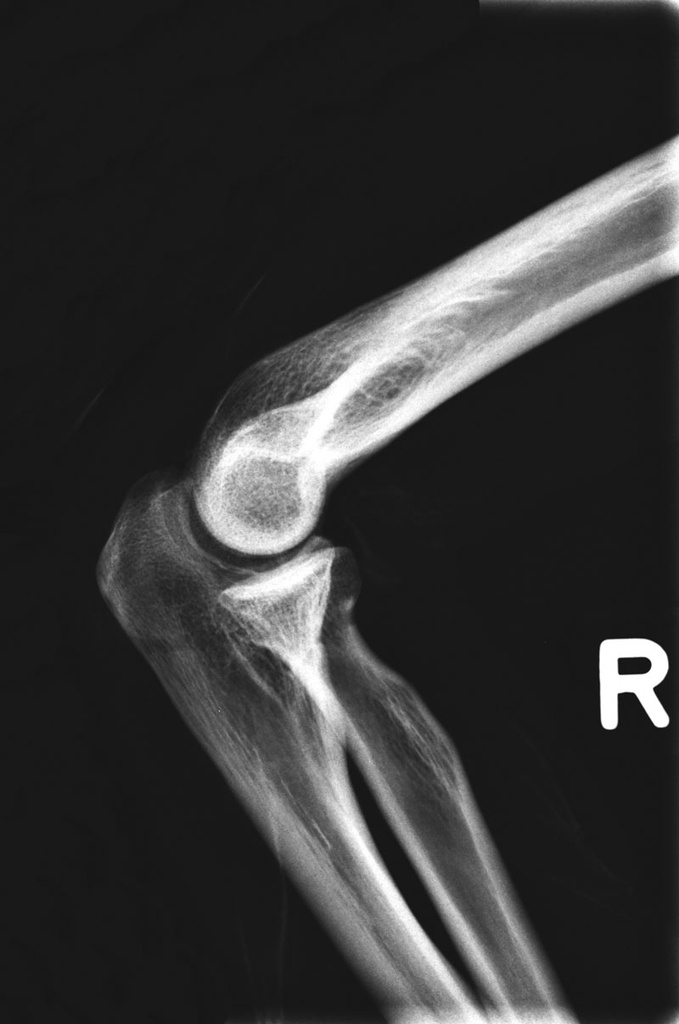

Dieses weltweit einmalige Phantom bietet erstklassige Übungsmöglichkeiten für die Lagerungs- und Einstelltechnik in der Projektions-Radiographie und gehört eigentlich zur Grundausstattung jeder Röntgen-Ausbildungsstätte. Das Phantom enthält ein natürliches menschliches Skelett sowie die Umrisse von Kehlkopf, Lunge, Herz und Nieren (Organe erscheinen als Schatten auf den Röntgenbildern), dadurch können mit dem Phantom echte Röntgenaufnahmen wie beim Patienten gemacht werden. Durch die Verwendung des echten Skeletts können Leitstrukturen im Knochen erkannt werden, was bei Kunststoffskeletten nicht möglich ist. Bei der Montage des Phantoms wird besonderer Wert auf die Darstellung der Gelenkspalte gelegt. Die Gelenke sind voll beweglich montiert, und ermöglichen die Lagerung in den normalen Röntgenpositionen (z.B. Froschposition, Pro- und Supination des Unterarms). Die Arme können nach oben bewegt werden, so dass das Modell auch für alle knöchernen Untersuchungen im CT verwendet werden kann. Bei jedem Phantom handelt es sich um ein handgefertigtes Unikat, welches sich in Größe und Ausführung unterscheiden kann. Je nach Modell können pathologische Befunde vorhanden sein, die äußere Erscheinung kann sich je nach Größe des Modells unterscheiden. Die neue Ausführung dieses Modells wurde in Zusammenarbeit mit einer namhaften deutschen Schule für Med. Techn. Radiologieassistenten komplett überarbeitet und erfüllt alle Anforderungen für die Ausbildung. Der Verkauf dieses Phantoms erfolgt nur gegen Nachweis der medizinischen Verwendung. Natürliche Größe.